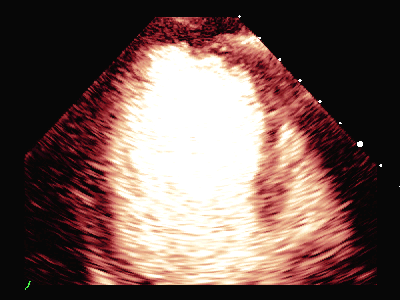

动态图(1)静息状态四腔心二维图

动态图(2)静息状态双平面LVO

超声负荷造影提示:

负荷前左室壁未见明确节段性运动异常,左室各节段心肌灌注充盈良好。

平板负荷量达89%时,该时患者心率157次/分,出现短阵性室性心动过速,即刻超声造影检查显示:负荷后左室前间隔中段、室间隔心尖段、侧壁中段、心尖段、下壁心尖段、前壁心尖段及心尖帽运动减弱。室间隔心尖段及心尖帽心肌灌注稀疏。

患者休息后检查:左室壁未见明确节段性运动异常,左室各节段心肌灌注充盈良好。